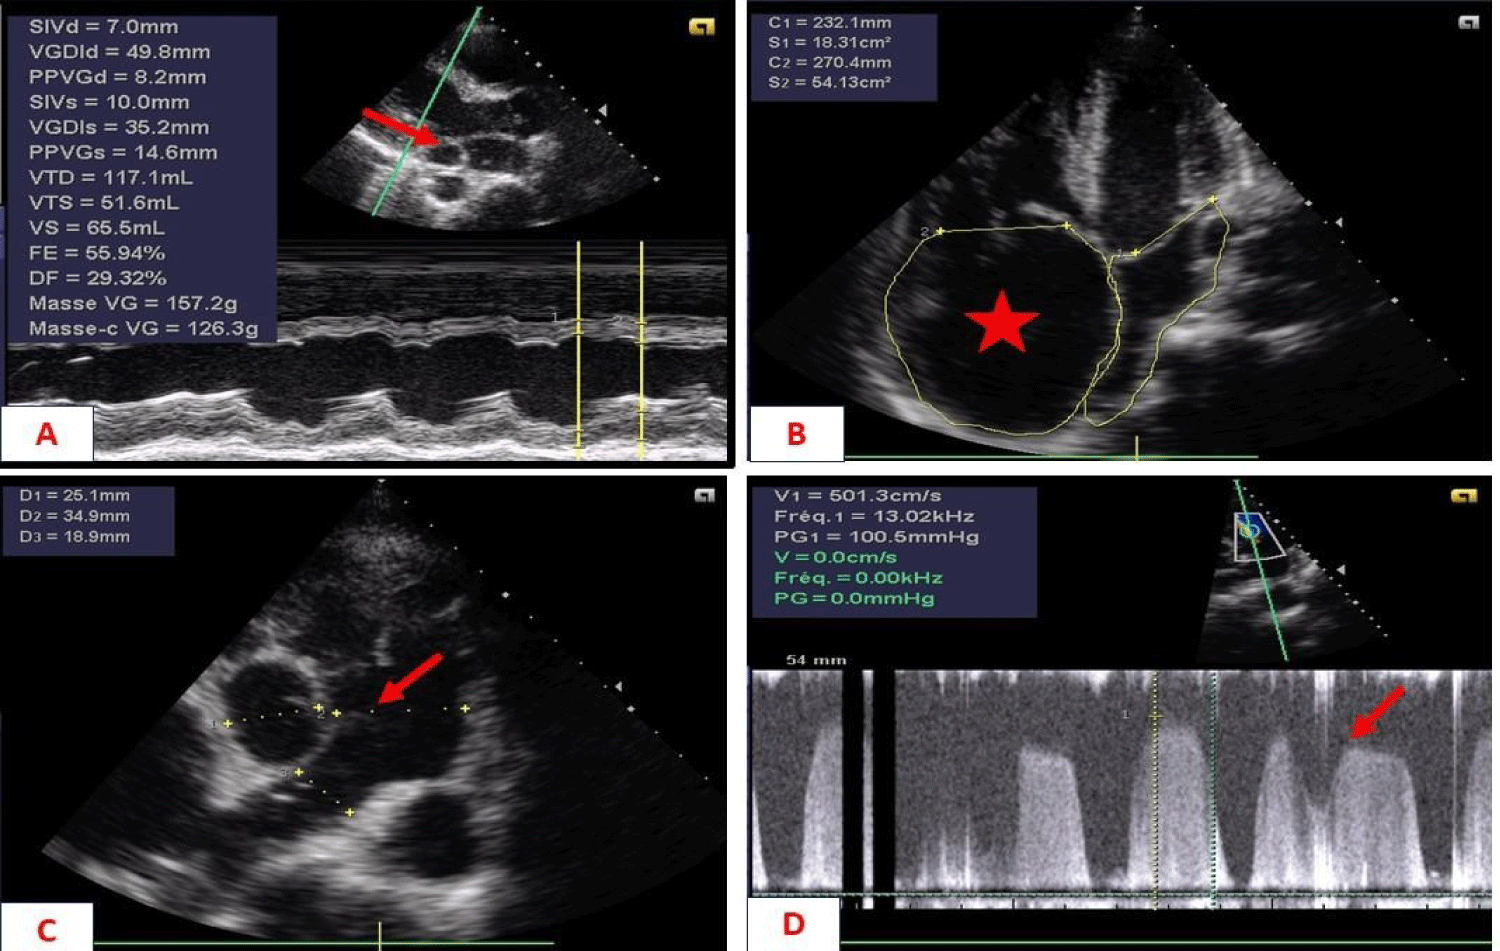

Biological tests showed polycythemia of 7 million/ul and mild anaemia of 11g/dL. The electrocardiogram showed atrial fibrillation (AF) with rapid ventricular response, while the X-ray showed significant cardiomegaly. Echocardiography showed a short-axis parasternal slice centred on the PA, with a tripod image and a left-right shunt between the aorta and PA. Continuous Doppler showed systolic flow in this shunt with diastolic extension without return to the isoelectric line. There was a passage of air bubbles into the left cavities (the patient had a venous line), dilatation of the coronary sinus, dilatation of the right cavities, and severe PAH at 90 mmHg. Echocardiography concluded that the patient had PCA with severe right-sided dilatation and severe PH associated with abnormal venous return. Chest CT showed the existence of two superior vena cava, one on the left and the other on the right, draining into the left and right atria respectively.

The patient was a 27-year-old mechanic with no known cardiovascular risk factors. He was admitted for syncope of sudden onset with no prodromal symptoms or associated signs. The patient had been suffering from permanent palpitations and exertional dyspnoea for several months. On physical examination, consciousness was clear, with blood pressure at 124/74 mmHg, tachycardia at 133 beats per minute and xiphoid tingling. Auscultation revealed irregular heart sounds with a tricuspid insufficiency murmur of intensity 4/6 and an aortic insufficiency murmur of intensity 3/6. Examination of the other equipment was normal. The electrocardiogram showed coarse-mesh atrial fibrillation with a rapid ventricular response of 140 cycles per minute (Figure 1). The chest X-ray showed cardiomegaly (cardiothoracic index = 0.75), a right inferior arch protrusion (dilatation of the right atrium), and a convex middle arch with an outward point (Figure 2). On Doppler echocardiography, there were visible bullae in the left cavities, significant dilatation of the right cavities, persistence of the ductus arteriosus, pulmonary hypertension (PAPS= 90 mmHg) and major dilatation of the coronary sinus in favour (Figure 3). The CT-scan also showed dilation of the right cavities and confirmed the presence of two superior vena cava, one on the right draining into the right atrium and the other on the left draining into the coronary sinus (Figure 4). The biology work-up showed polycythemia at 7 million/ul and mild anaemia at 11g/dL. The diagnosis was persistent CA and SCAV complicated by AF. The patient was treated with a curative dose of Enoxaparin followed by Rivaroxaban and Amiodarone. The course was marked by the onset of cardiovascular collapse refractory to vasopressive amides, followed by death on the seventh day of hospitalisation.